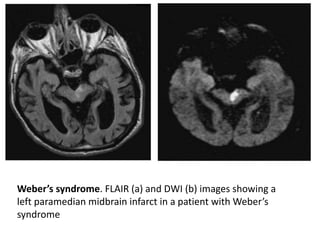

Weber’s syndrome. FLAIR (a) and DWI (b) images showing a

left paramedian midbrain infarct in a patient with Weber’s

syndrome